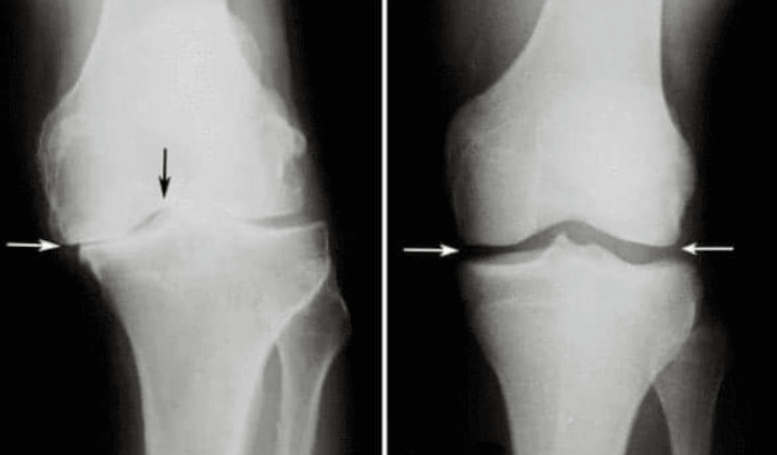

Martin Repko: Hlavní příčinou problémů s klouby a páteří je nedostatečná produkce kloubní mazi.

Kloubní maz totiž funguje jako přirozené mazivo. Když není jeho dostatek, klouby se opotřebovávají a poškozují. Nejvíce postihnutá jsou kolena, prsty, lokty a páteř.

Martin Repko: Hlavní komplikace patologie kloubů zahrnují změnu tvaru kloubu, výrazné omezení pohybu a ztuhlost, která kloub zcela imobilizuje, často v nesprávné pozici.

V případě neúplného ohybu a natažení kloubů se mění osy končetin, podél kterých se rozkládá hlavní mechanická zátěž těla. V důsledku systematického narušení správné osy končetiny se zvyšuje zatížení ostatních kloubů, což vede k sekundárním degenerativním změnám.